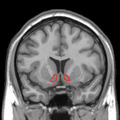

![]() Approximate location of the nucleus accumbens in the brain | |

The nucleus accumbens (NAc or NAcc; also known as the accumbens nucleus, or formerly as the nucleus accumbens septi, Latin for "nucleus adjacent to the septum") is a region in the basal forebrain rostral to the preoptic area of the hypothalamus.[1] The nucleus accumbens and the olfactory tubercle collectively form the ventral striatum. The ventral striatum and dorsal striatum collectively form the striatum, which is the main component of the basal ganglia.[2] The dopaminergic neurons of the mesolimbic pathway project onto the GABAergic medium spiny neurons of the nucleus accumbens and olfactory tubercle.[3][4] Each cerebral hemisphere has its own nucleus accumbens, which can be divided into two structures: the nucleus accumbens core and the nucleus accumbens shell. These substructures have different morphology and functions.